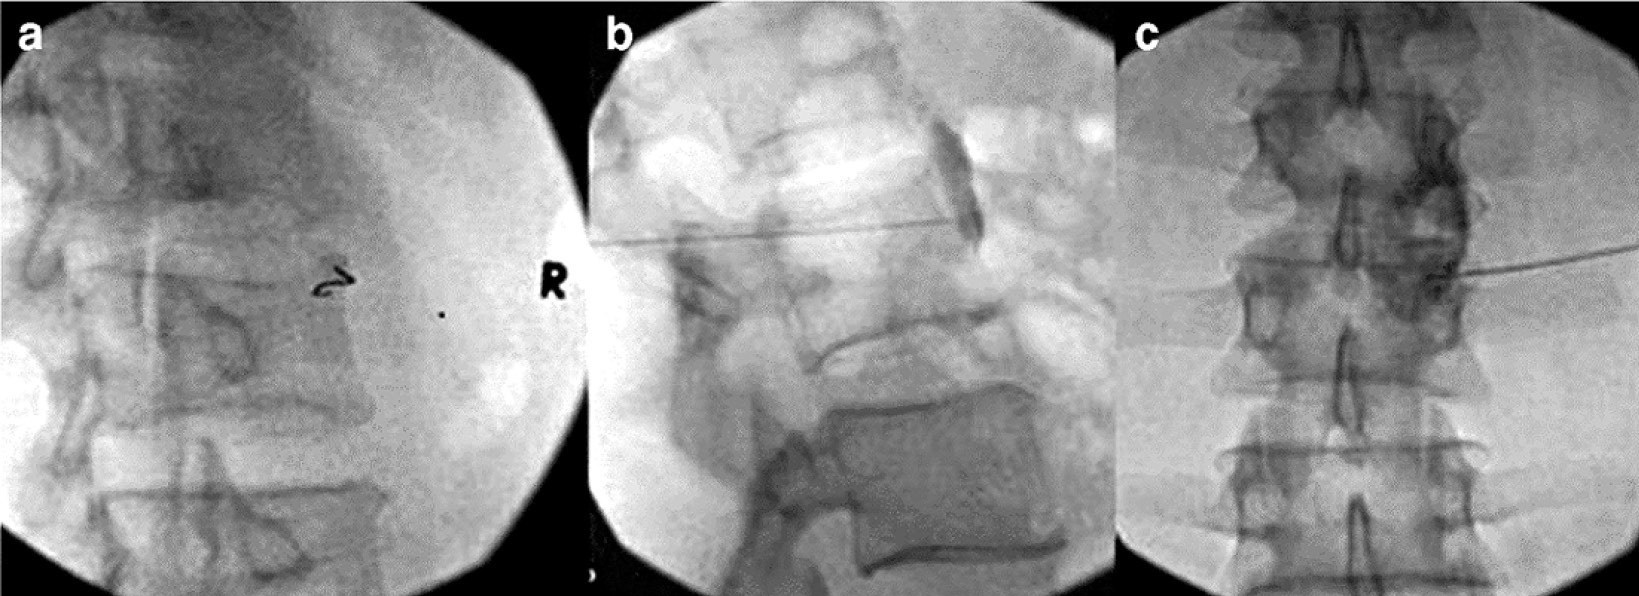

Поясничные симпатические блокады. Для лечения КРБС нижних конечностей применяется поясничная симпатическая блокада. Поясничные симпатические ганглии расположены передне-латерально по отношению к телам поясничных позвонков рядом с поясничной мышцей. Может быть от 3 до 5 ганглиев, которые могут быть разделены или слиты. Анатомическое расположение поясничных симпатических ганглиев может сильно различаться у разных людей, исследования на трупах показали, что L3 является наиболее распространённым уровнем [51]. Поясничные симпатические блокады обычно выполняются на уровне L3 или на уровне L2 и L4. Был предложен новый подход для более прямого воздействия на область диска L2–3 посредством парадискального, экстрафораминального доступа [52]. По мнению авторов, при попадании иглы в верхнюю часть тела позвонка L3 снижается риск непреднамеренного проникновения в диск L2–3 (рис. 4). Кроме того, большой объём местного анестетика позволяет охватить большую анатомическую область, делая точку входа немного менее важной для общего успеха блокады по сравнению с блокадой звёздчатого ганглия. Помещение иглы в брюшко поясничной мышцы является распространённой ошибкой, поэтому как боковая, так и передняя рентгеноскопия являются обязательными для подтверждения правильного положения иглы и распределения контраста. В то время как рентгеноскопия является основным методом визуализации, также используются ультразвук, магнитно-резонансная томография (МРТ) и компьютерная томография (КТ) [52, 53].

Рис. 4. Блокада поясничного симпатического ганглия под рентгеноскопическим контролем: а – косая проекция, игла контактирует с костью над поперечным отростком на уровне L3; b – вид сбоку, кончик иглы на переднем крае L3, превертебральное распространение контраста; c – вид спереди, контраст распространяется к средней линии L3 с дольчатым «облачным» рисунком [48] / Fig. 4. Blockade of the lumbar sympathetic ganglion under fluoroscopic control: a – oblique projection, the needle is in contact with the bone above the transverse process at the level of L3; b – lateral view, needle tip at the anterior margin of L3, prevertebral spread of contrast; c – anterior view, the contrast extends to the L3 midline with a lobed “cloudy” pattern [48]